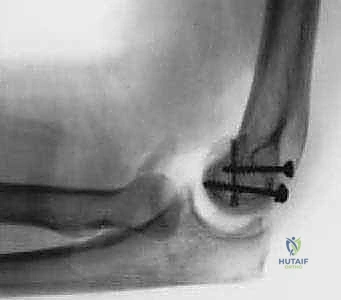

TECH FIG 1 • Fixation of a type 1 capitellum fracture with a headless screw anteriorly and AO screws from posterior to anterior.

Definitive Internal Fixation: Our choice of hardware depends on the fracture type and the amount of subchondral bone present.

- Headless Compression Screws (e.g., Herbert screws): These are ideal for fragments with less subchondral bone, such as Type 2 fractures and smaller Type 1 fragments. They offer excellent compression and can be inserted from either anterior-to-posterior or posterior-to-anterior.

* **AO Cancellous Screws:** These are best suited for Type 1 fracture fragments with a large subchondral component. They are typically placed from posterior-to-anterior.